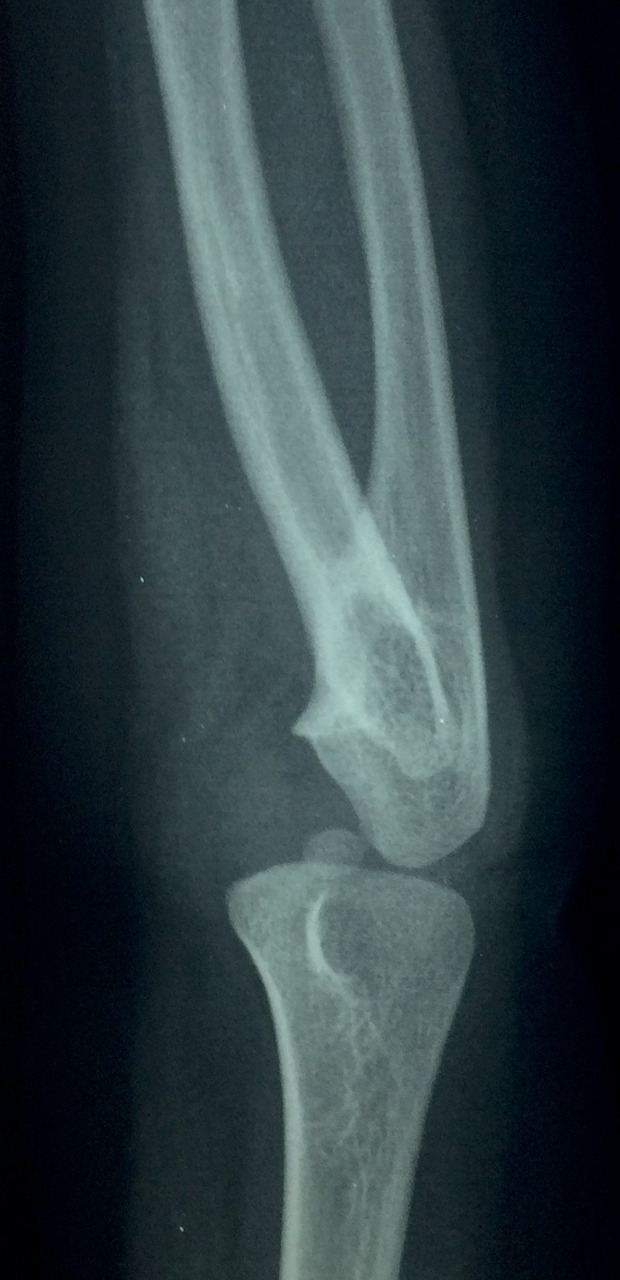

À la radiographie de l’avant-bras et du coude : fusion des parties proximales de radius et de l’ulna (fig. 1 et 2).

La synostose radio-ulnaire congénitale, avec fusion plus ou moins complète des épiphyses proximales du radius et de l’ulna, est une affection rare : environ 350 cas recensés dans la littérature. Elle est bilatérale dans 60 % des cas, et prédomine chez les hommes (3 pour 2 femmes).

Parfois associée à d’autres malformations (aplasie du pouce), voire aux syndromes de Carpenter, d’Apert ou de Klinefelter, elle correspond à un défaut de séparation embryonnaire des os vers la cinquième semaine de développement. Le pont cartilagineux s’ossifie et fixe l’avant-bras en pronation. Les muscles supinateurs et pronateurs sont anormaux ou absents, la membrane interosseuse épaissie. La tête radiale peut être hypoplasique, luxée ou absente, et l’épiphyse ulnaire distale déformée.